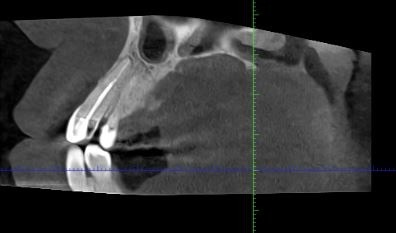

1.3 Хронический апикальный периодонтит.

Длина корневого канала 24 мм.